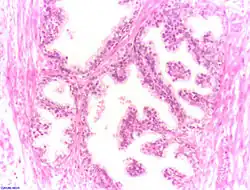

Dans l'HBP, l'architecture de la prostate est globalement préservée avec un aspect nodulaire, mais il existe une hyperplasie des différents constituants.

Les glandes prostatiques sont en nombre augmenté, bordées par une double assise épithéliale. Elles sont souvent le siège de dystrophie (kystisation) ou d'atrophie, et de phénomènes inflammatoires. Les cellules musculaires lisses sont également en nombre augmenté, de même que les fibroblastes de l'interstitium.

L'hyperplasie respective des différents constituants (épithélial, musculaire lisse et fibroblastique) est d'intensité variable suivant les territoires examinés.

Prostatectomie et adénomectomie sus-pubienne

Histologie d'une prostate normale |

Histologie d'une hypertrophie bénigne de la prostate |